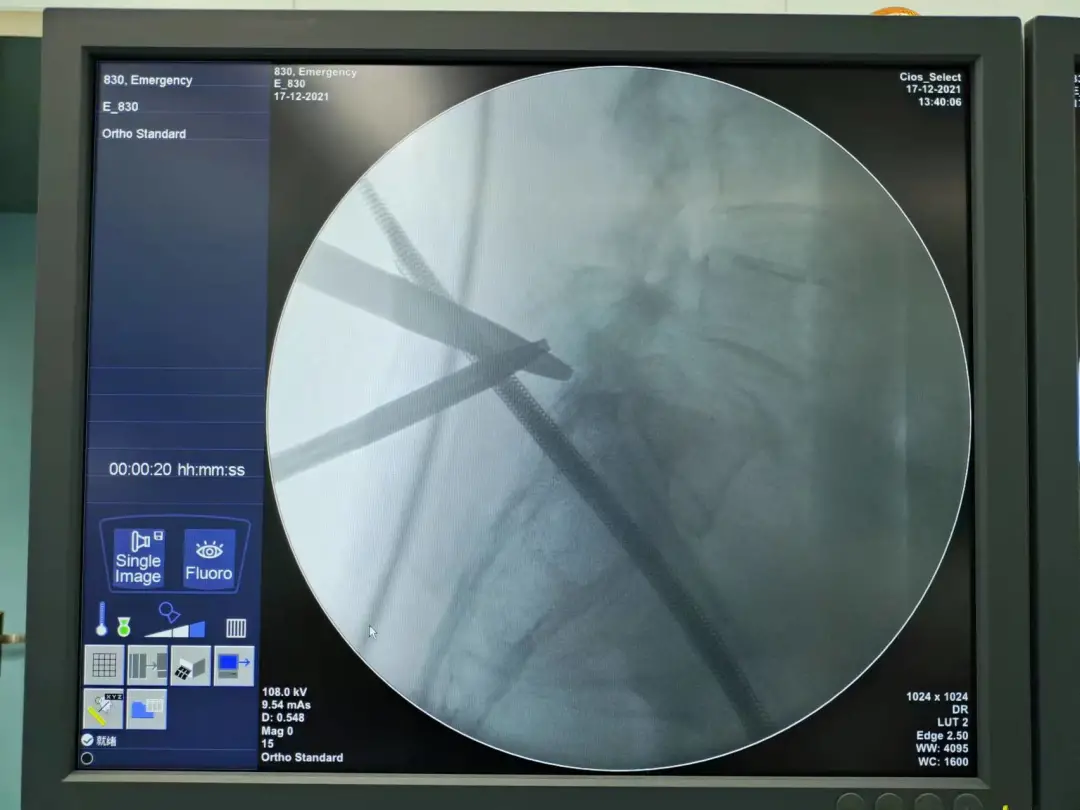

完善术前相关检查后,12月17日,肖林团队为李女士施术,以UBE技术成功扩宽了腰椎管,手术无血。术后,李女士腰腿疼痛缓解明显。

肖林正在为李女士清理腰椎管